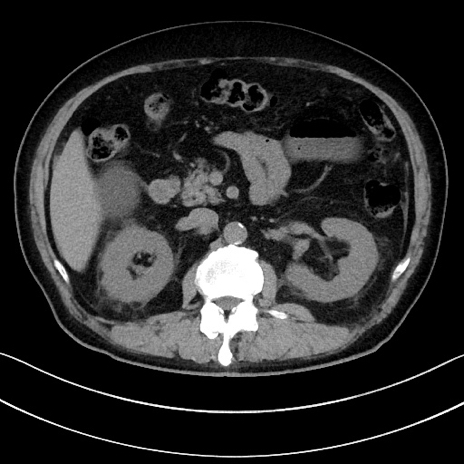

症例15(横断像)

【症例】70歳代男性

【主訴】腹痛

【現病歴】今朝から腹痛あり。全体的に痛い。特に左上の方。排ガスが今日はない。冷や汗が出る。

【既往歴】直腸癌術後

【身体所見】左側腹部〜上腹部に圧痛あり。腹膜刺激症状明らかなではない。軽度反跳痛。左下腹部に術後瘢痕あり。

【データ】WBC 7700、CRP 0.02